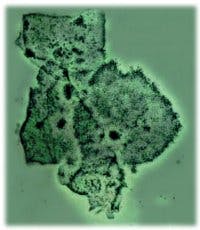

Clue cell is a term for vaginal SECs that are coated with tiny coccobacilli such that the SEC border is obliterated or appears shaggy and may be dense enough to partially obscure the nucleus.3 The presence of clue cells in vaginal secretions is one of four findings used for the diagnosis of bacterial vaginosis (BV). Other laboratory signs include a vaginal pH greater than 4.5, a positive whiff test (fishy odor on addition of 10 percent KOH to vaginal secretions), and abnormal vaginal flora (absence of lactobacilli and increase of Gardnerella and anaerobes). Usually clue cells are visualized in vaginal wet mounts or stained smears. Although the presence of clue cells in urine sediment indicates a poorly collected specimen, it suggests that the woman may have BV and should be noted on the urinalysis report.